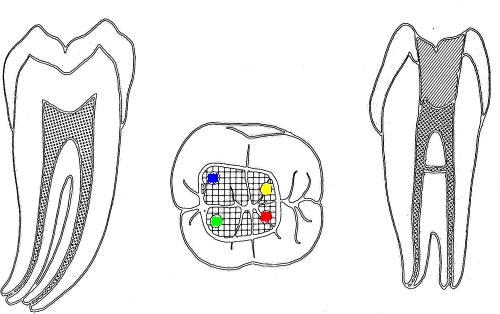

| 2º molar inferior (1,2,23,27)

Similar al primer molar inferior pero menos voluminoso, en la

raíz mesial siempre encontrará dos conductos y en la raíz distal

puede encontrar uno ó dos conductos.

En azul conducto mesiovetibular

-

En verde conducto mesiolingual

En rojo conducto distal

En amarillo un cuarto conducto,

si el conducto distal se encuentra desplazado hacia lingual,

existe una alta posibilidad de encontrar un cuarto conducto

|

| 1º Molar

inferior: El orificio de entrada del

conducto distal se encuentra ensanchado

en sentido buco lingual, debe sospechar

la existencia de un cuarto conducto.

La localización

de un cuarto conducto se lleva a cabo

con la

técnica radiológica de Clark

o por

medio de una lima curvada en distal para

sondear la pared lingual ó vestibular

del conducto distal. Imagen inferior |